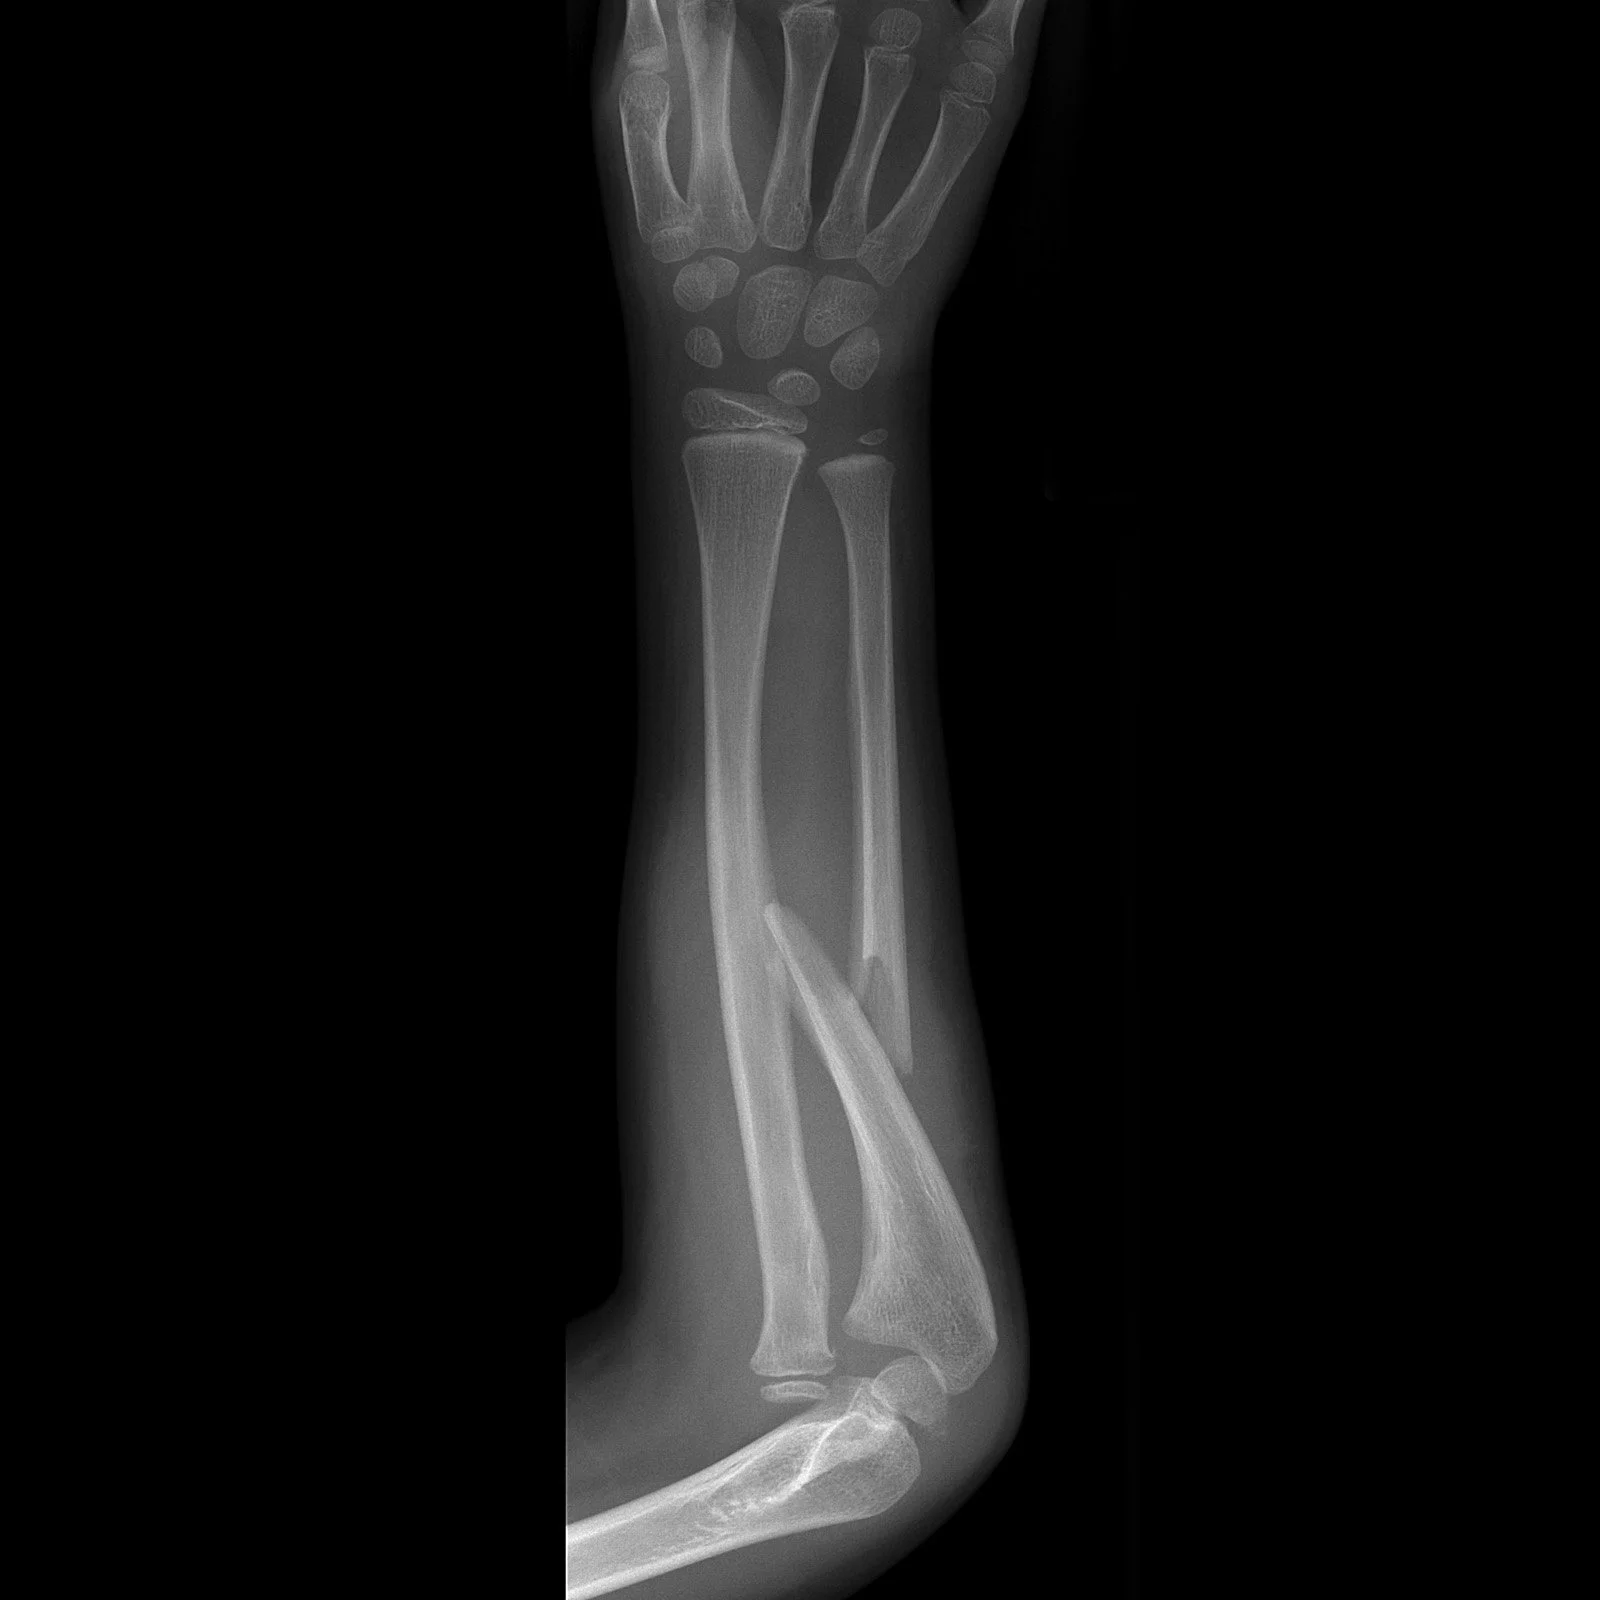

Monteggia

• Fracture of ulnar shaft with dislocation of radial head.

• Further classified by Bado system:

• Class 1: Anterior dislocation of radial head (most common).

• Class 2: Posterior dislocation of the radial head.

• Class 3: Lateral or antero-lateral dislocation of the radial head.

• Class 4: Anterior radial head dislocation as well as proximal third ulnar and radial shaft fractures.

Case courtesy of Frank Gaillard, Radiopaedia.org, rID: 8012 (Monteggia case)